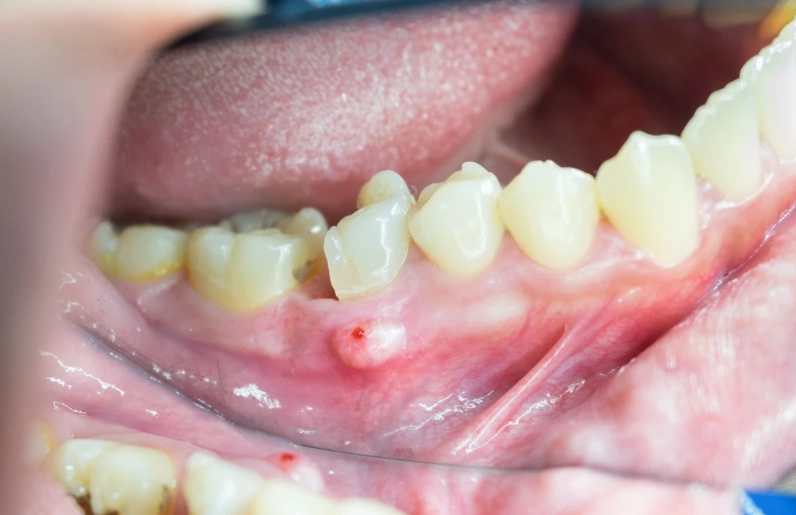

The specific code is K04.7 - Periapical abscess with sinus. Now, the 'with sinus' part confuses everyone at first. In dental terms, a 'sinus' here doesn't refer to your nasal sinuses. It means a sinus tract – a small, channel-like opening that the abscess creates to drain pus, often appearing on the gum as a pimple-like bump called a 'parulis' or 'gum boil.' This is the body's attempt to relieve pressure.

Then comes the clinical exam. They'll visually check the tooth and gums, looking for cavities, large fillings, cracks, or that tell-tale gum boil (sinus tract). They'll gently tap (percuss) on several teeth. The infected one will often feel exquisitely tender to this tapping. They might use a cold test (a quick shot of cold air or a cotton pellet with a freezing agent) on the tooth. A dead tooth won't feel the cold at all, while a dying one might have a prolonged, painful response.